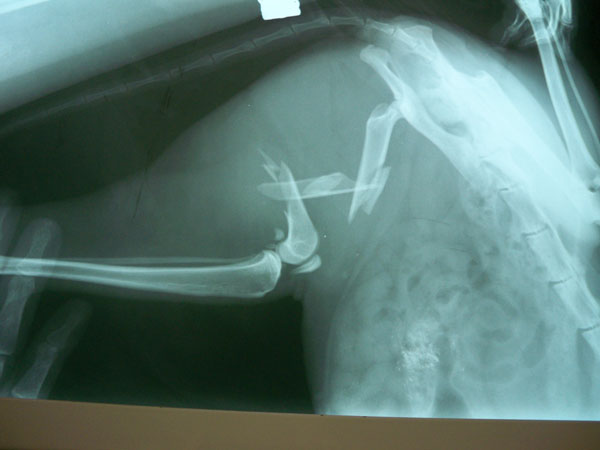

Συντριπτικό κάταγμα μεσότητας διάφυσης δεξιού μηριαίου γάτας.

Η Gogo είναι μιά γάτα 2 ετών με συντριπτικό κάταγμα στον μηρό. Χειρουργήθηκε και τώρα μετά την οστεοσύνθεση, το άκρο είναι απόλυτα λειτουργικό.

Οι ακτινογραφίες είναι πρίν και μετά το χειρουργείο.